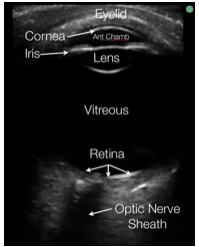

Imaging: FAST, further imaging as indicated by injuries/suspicion of clinician. Imaging should not be delayed or deferred 2/2 concern for fetal radiation exposure in the trauma setting!!!!